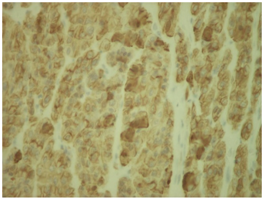

Pathological examination of the tissue sections revealed a 1,5 cm circumscribed neoplasm with tan color partially encapsulated, covered by healthy parotid tissue. A lymphe node 2,1 cm was also present but had non specific reactive changes. The neoplasm had a nested pattern of growth suggesting an oncocytoma. It composed of cells with vesicular nuclei, with prominent nucleoli and abundant granular acidophilic cytoplasm. (Figure 1) (Figure 2). Enhanced mitosis, cytological atypia, moderate nuclear pleomorphism and necrosis were noted. Focally an abnormal circumference with connective tissue and fibrous elements was also present suggesting that this neoplasm has agressive histological features with malignant potential. Immunohistological staining pattern showed that the neoplastic cells had a Ki67 positive at 8% (Figure 3), positve for ker 8/18 (Figure 4), positive-negative for p63 while were negative for ker 14, SMA, CEA, TTF-1, CD31, calcitonin, EMA, GFAP, and S100 staining.

Figure 4 Ker 8/18: Postive at the neoplastic cells.